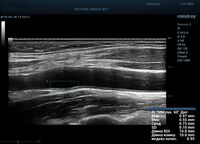

Функция в ультразвуковых аппаратах

На сегодняшний день измерение IMT происходит автоматическим путем при использовании функции AUTO-IMT. Необходимо указать прибору зону интереса, стандартной длиной (1 см), в которой происходит отслеживание кромок и выдача максимального, среднего и минимального значения. УЗИ аппараты компании Mindray среднего, экспертного и премиального класса снабжены данной функцией и позволяют контролировать не только полученные значения, но и оценить точность измерения кромки в конкретной зоне по индексу качества. Используя индекс качества, легко решить, можно ли использовать полученное значение.

Форма отчета стала удобной: в единой таблице сводятся измерения левых и правых артерий, указываются все значения с автоматическим расчетом общего среднего показателя. Если один из показателей измерения резко выбивается и считается недостоверным – его можно исключить из расчета.